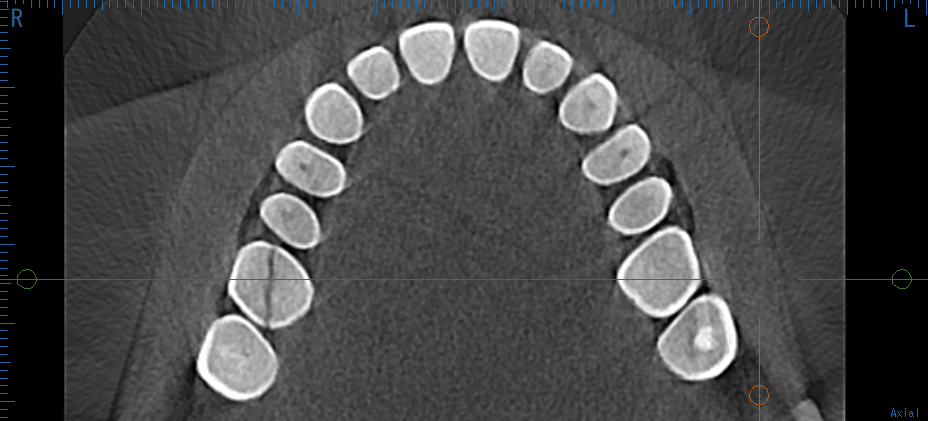

気になってCTを撮影してみると、 奥歯の歯根が真っ二つに割れていた(歯根破折) のです。

CTを撮影してみると一目瞭然。奥から2番目の歯がまっぷたつに割れています。